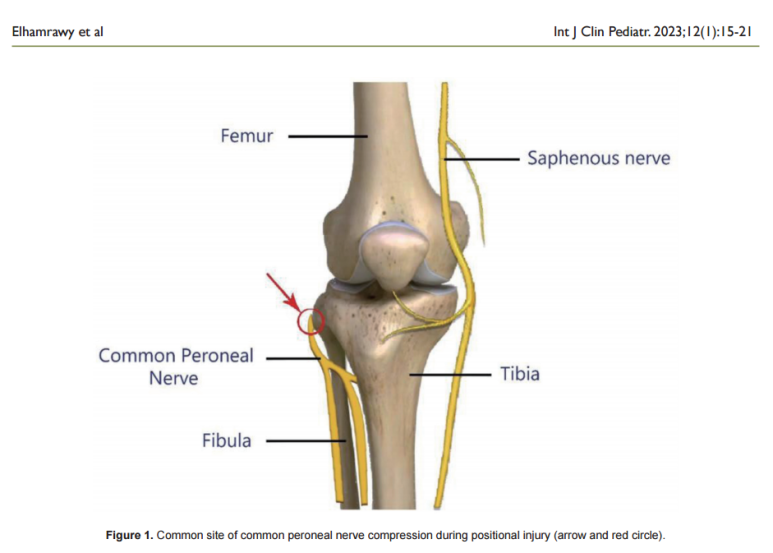

@ https://doi.org/10.14740/ijcp513

이 신경은 무릎 바깥쪽에 튀어나온 뼈인

'비골두(fibular head)'를 끼고

피부에서 가까운 아주 얕은 곳으로 지나갑니다.

주변에 근육이나 지방 같은 쿠션이 거의 없어서

외부 압박에 매우 취약하죠.